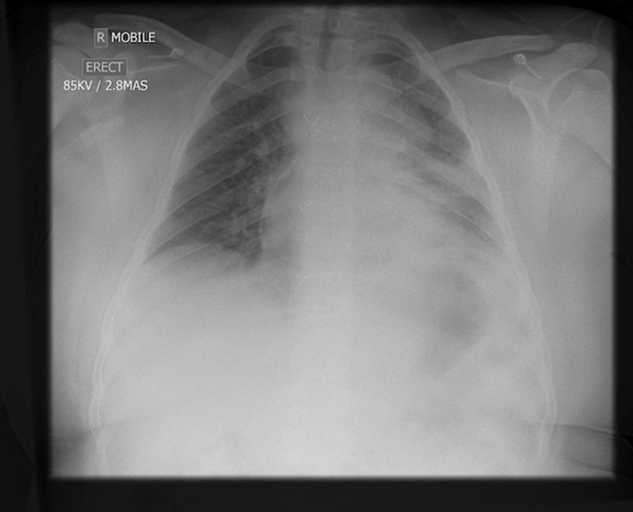

On day 7 of his illness, he deteriorated requiring an increase in his oxygen requirement to 1 L/min, and his chest x-ray showed significant left mid and lower zone consolidation (Fig 1). He was commenced on intravenous cephalosporin and oral macrolide antibiotics. There had been ongoing liaison since his initial presentation with paediatric cardiology and respiratory specialists, and it was decided with the deterioration to transfer to a tertiary paediatric hospital.

Figure 1. Chest X-ray day 7.